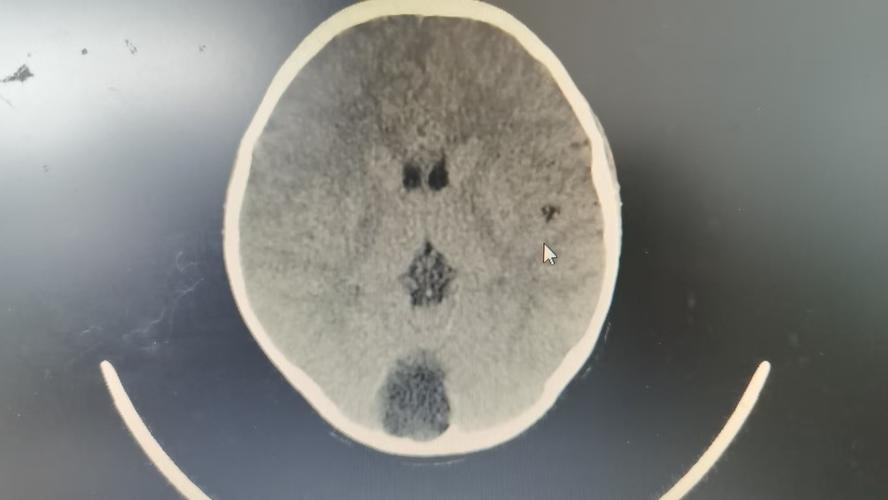

(图片来源网络,侵删)

总结一下:儿童蛛网膜囊肿的症状多种多样,从无症状到严重的颅内压增高都有可能,家长不必过度焦虑,因为绝大多数情况是良性的,但一旦发现上述异常信号,及时就医,通过头部CT或MRI进行明确诊断,并由专业医生评估是否需要治疗,是至关重要的。